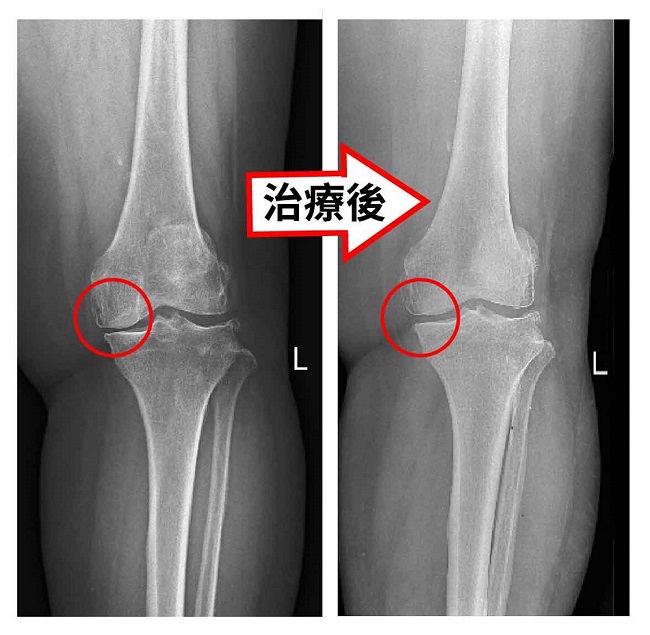

經過我們膝望工程「以修理替代換關節」的觀念治療下,運用中西結合的超微創治療技術,已經可以把關節修整到恢復日常活動使用無虞的程度。,我們可以從李呂女士治療前跟治療後的關節X光片來做對比,可以明顯看出膝關節的骨頭邊緣以及關節的間隙都明顯改善許多,像李呂女士這樣全身慢性病開刀風險高,或是打過PRP 又沒有效的老人家,可以優先考慮這項創新不動刀又確實有效的治療方式。